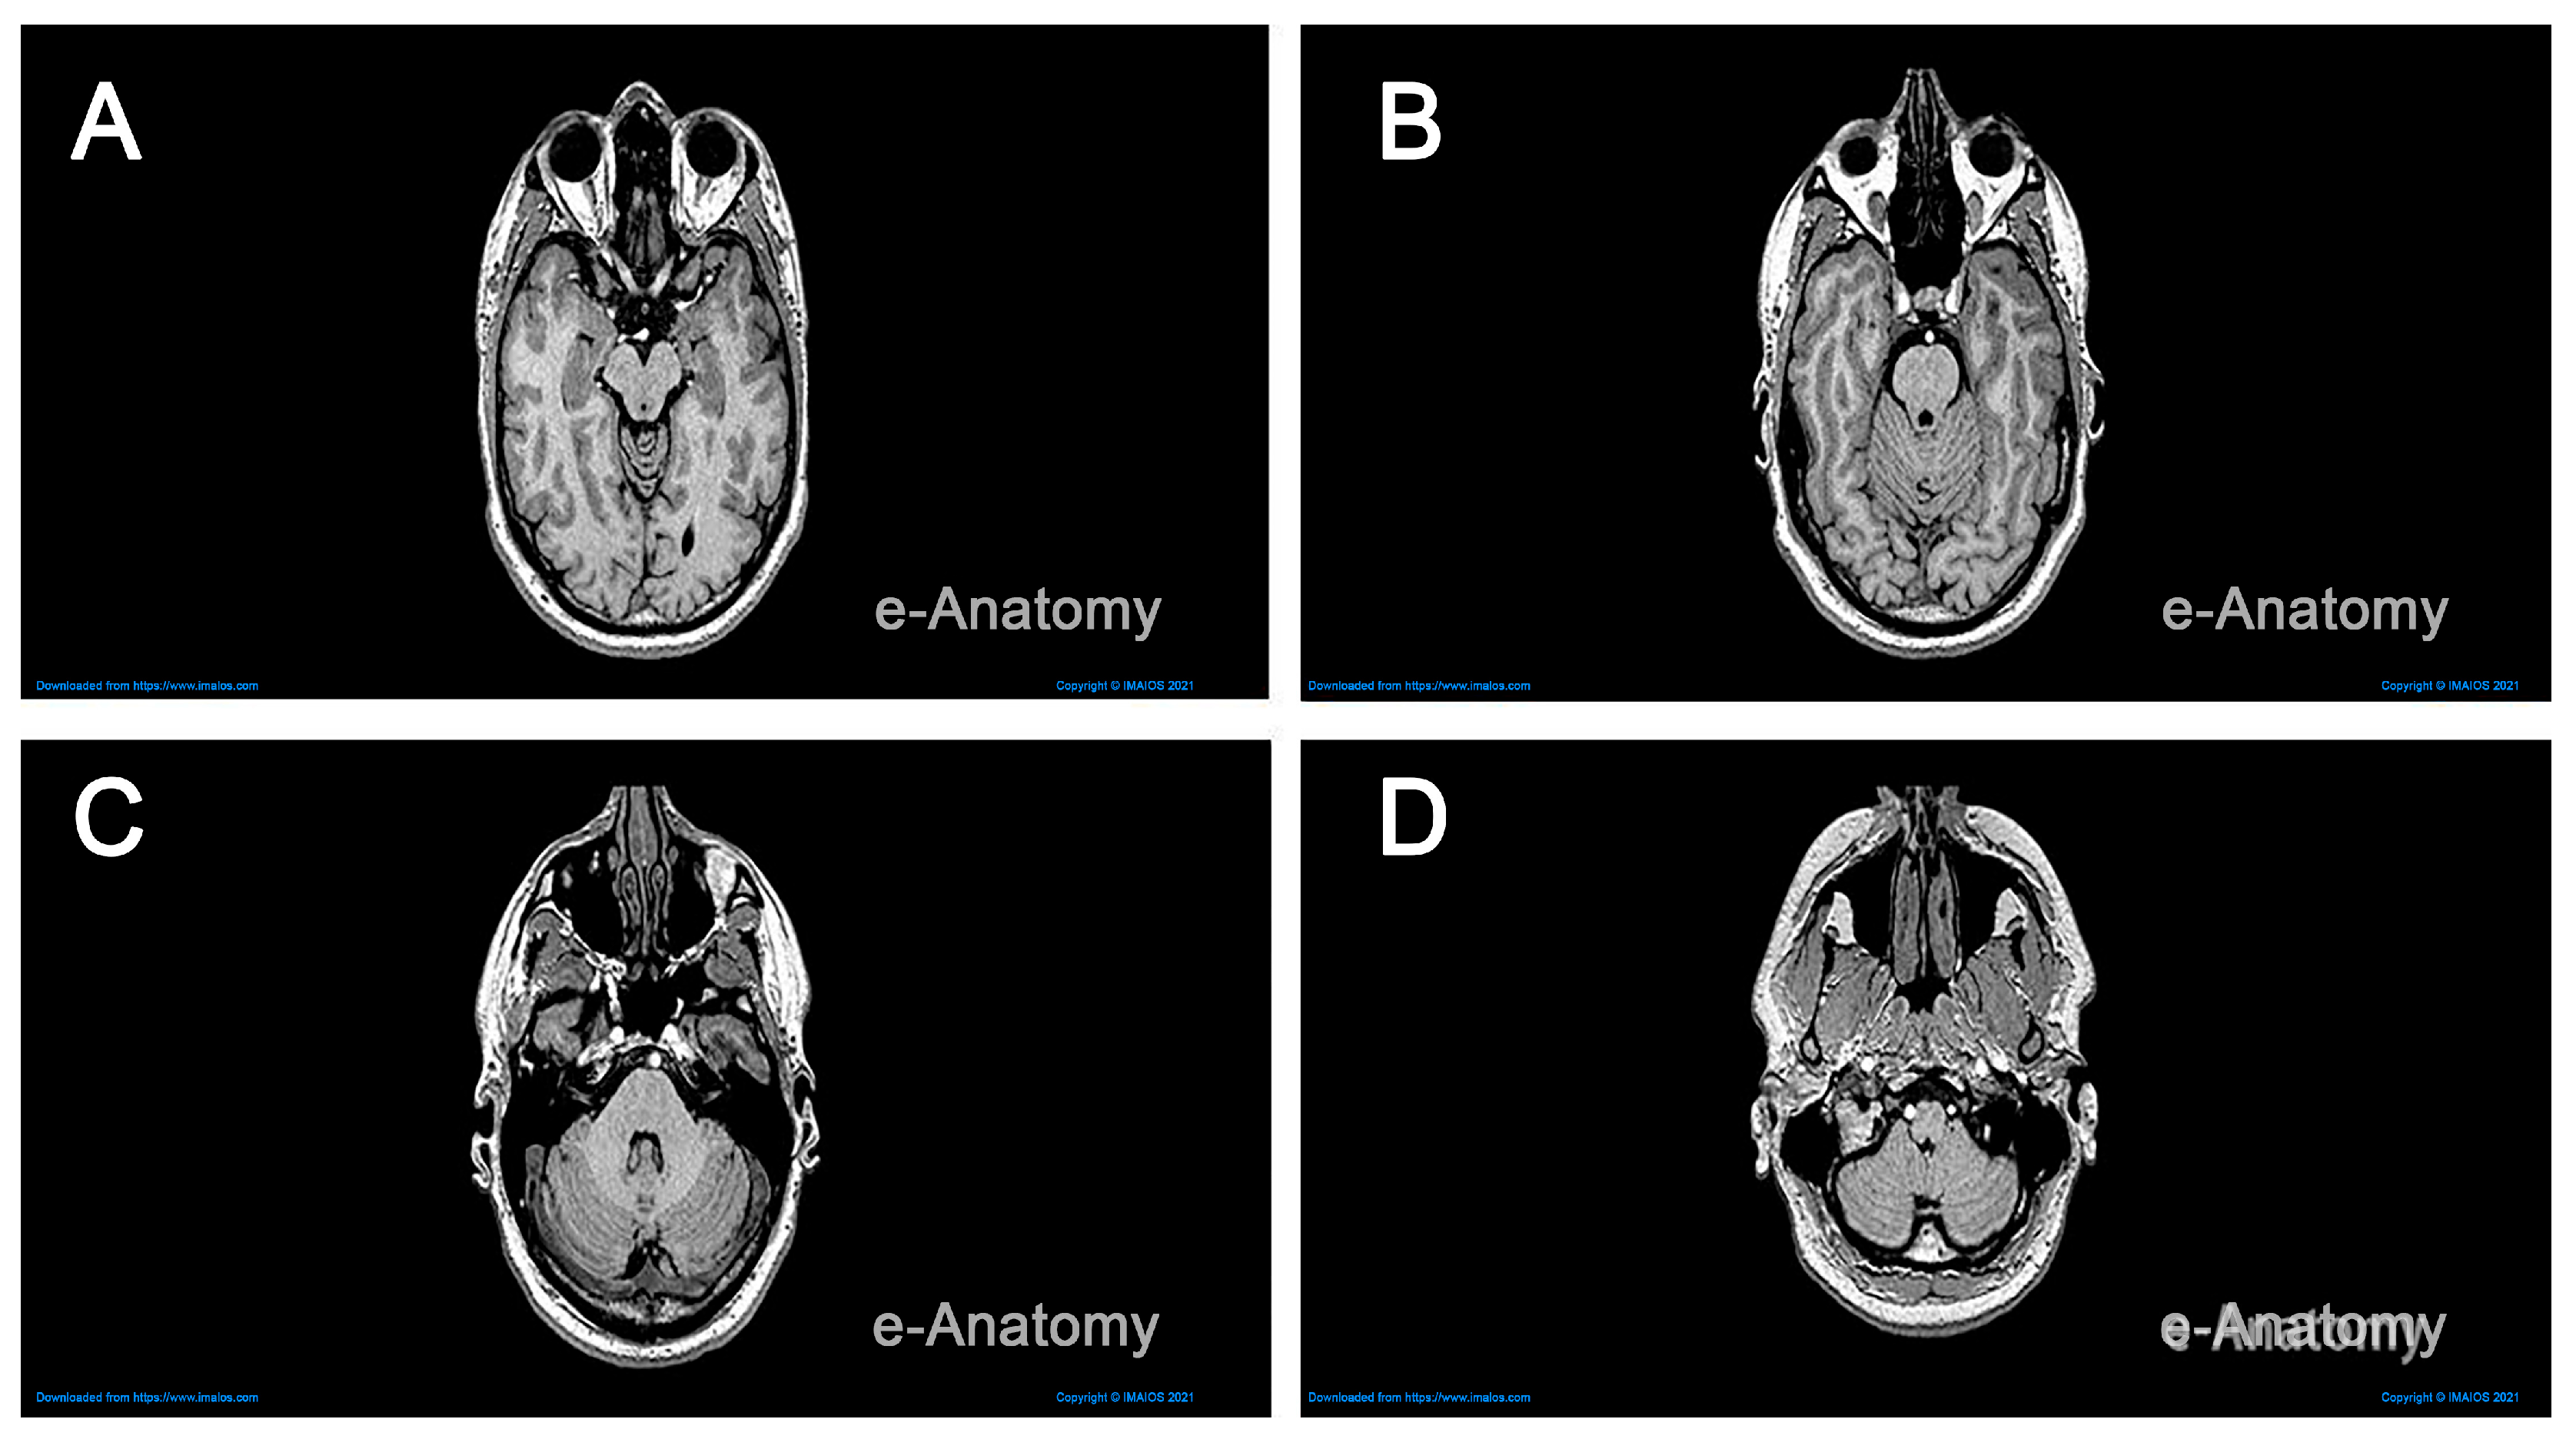

2.1. Data Collection

- Micheau, A.; Hoa, D. e-Anatomy. 2008. Available online: https://doi.org/10.37019/e-anatomy (accessed on 28 October 2023).